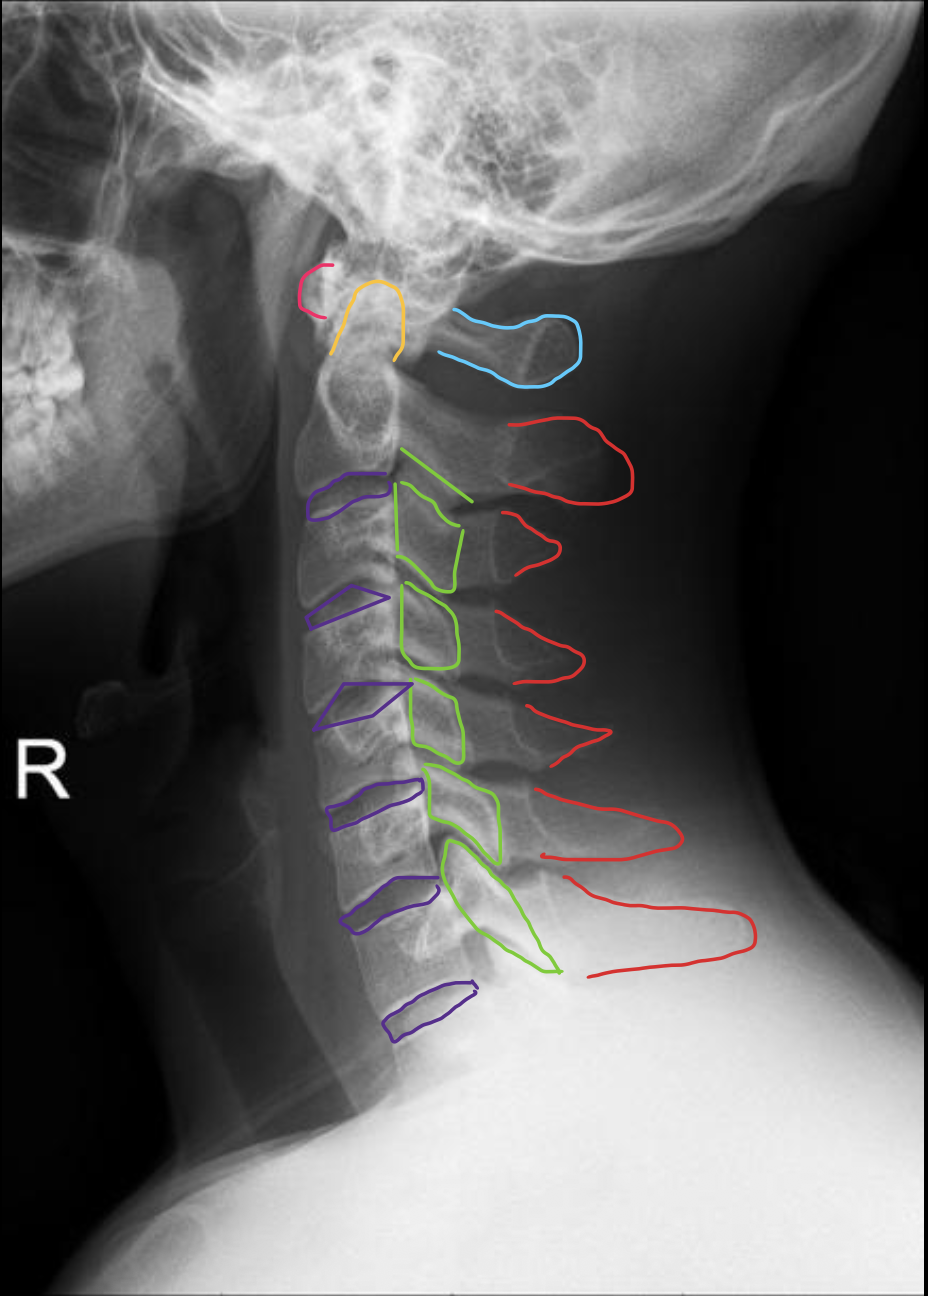

C1

C2

C3

C4

C5

C6

C7

T1

1st rib

寰椎前结节

C1 anterior tubercle

寰椎后弓及后结节

C1 posterior arch & tubercle

关节突

Articular process

椎间孔

Intervertebral Foramina

椎弓根

Pedicle

椎间盘

Intervertebral disc

关节突关节(小关节)

Zygapophyseal

齿状突(枢椎齿突)

Odontoid

Posterior arch & Tubercle of C1

棘突

Spinous process

椎间盘(Intervertebral Disc)

IVD

寰椎前弓

Anterior arch of C1

椎板棘突线(椎弓后缘线)

Spinolaminar

棘突后缘线

Posterior spinous

椎体

Vertebral body

椎板

Lamina

关节突关节

Zygapophyseal joint

IVD (Intervertebral Disc)

分叉棘突

Bifid Spinous process